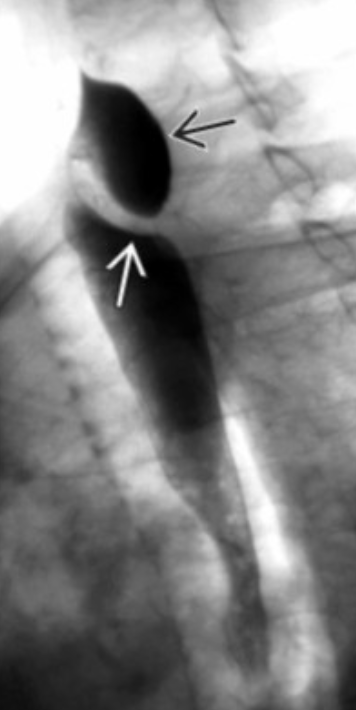

Zenker Diverticulum

• Posterior

• Just above cricopharyngeus muscle

Killian-Jamieson Diverticula

• Rarest form of esophageal diverticula

• Anterolateral wall of cervical esophagus

• Below cricopharyngeus muscle

• Usually smaller and obv anterior compared to zenker